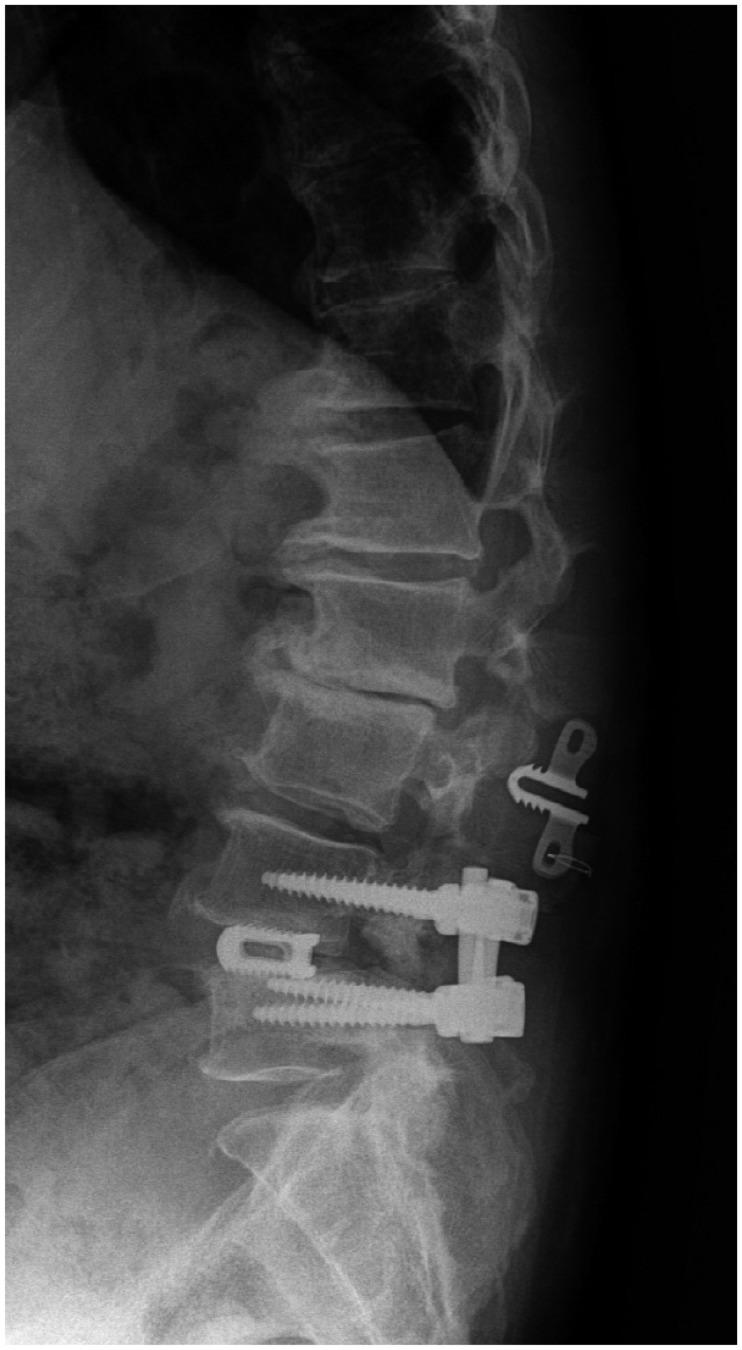

Lumbar fusion using the pedicle screw system is a popular operative procedure, with favorable clinical results and high fusion rates. However, the risk of adjacent segment disease after lumbar fusion is problematic. We report a complicated case of severe retrolisthesis at L3-4 level following dynamic interspinous process stabilization at L2-3 level and a fusion at L4-5 level. The radiological and clinical findings of this complication are discussed, and a review of the literature is presented.

使用椎弓根螺钉系统进行腰椎融合是一种常见的手术方法,临床效果良好且融合率高。然而,腰椎融合术后相邻节段疾病的风险是个问题。我们报告了一例复杂病例,在L2 - 3节段进行动态棘突间稳定术以及L4 - 5节段融合术后,L3 - 4节段出现严重的椎体后滑脱。本文讨论了该并发症的影像学和临床发现,并对相关文献进行了综述。